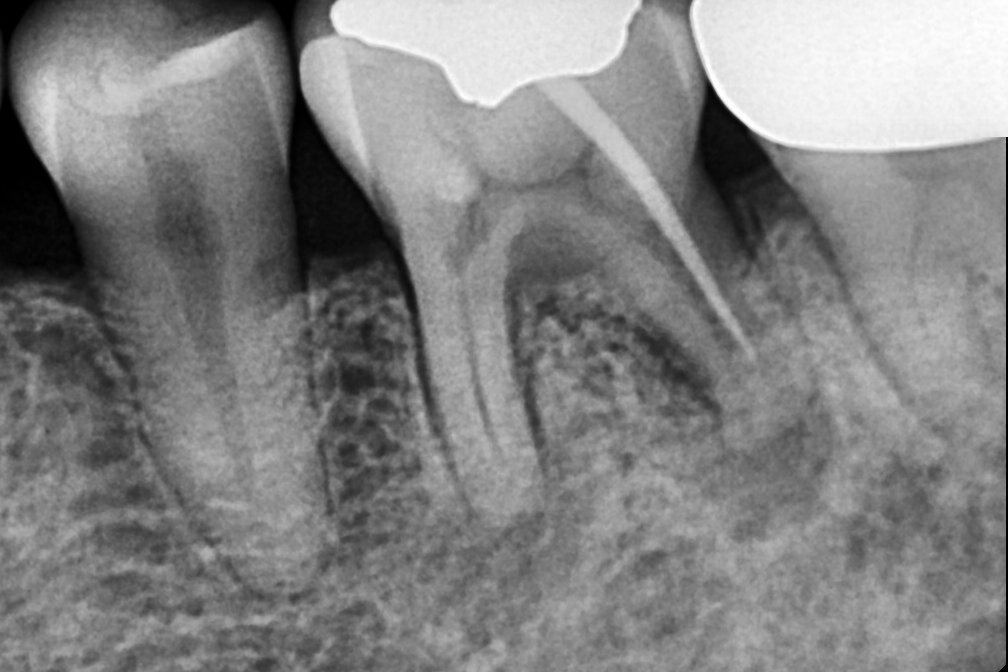

신경치료

Before 2025년 11월 25일